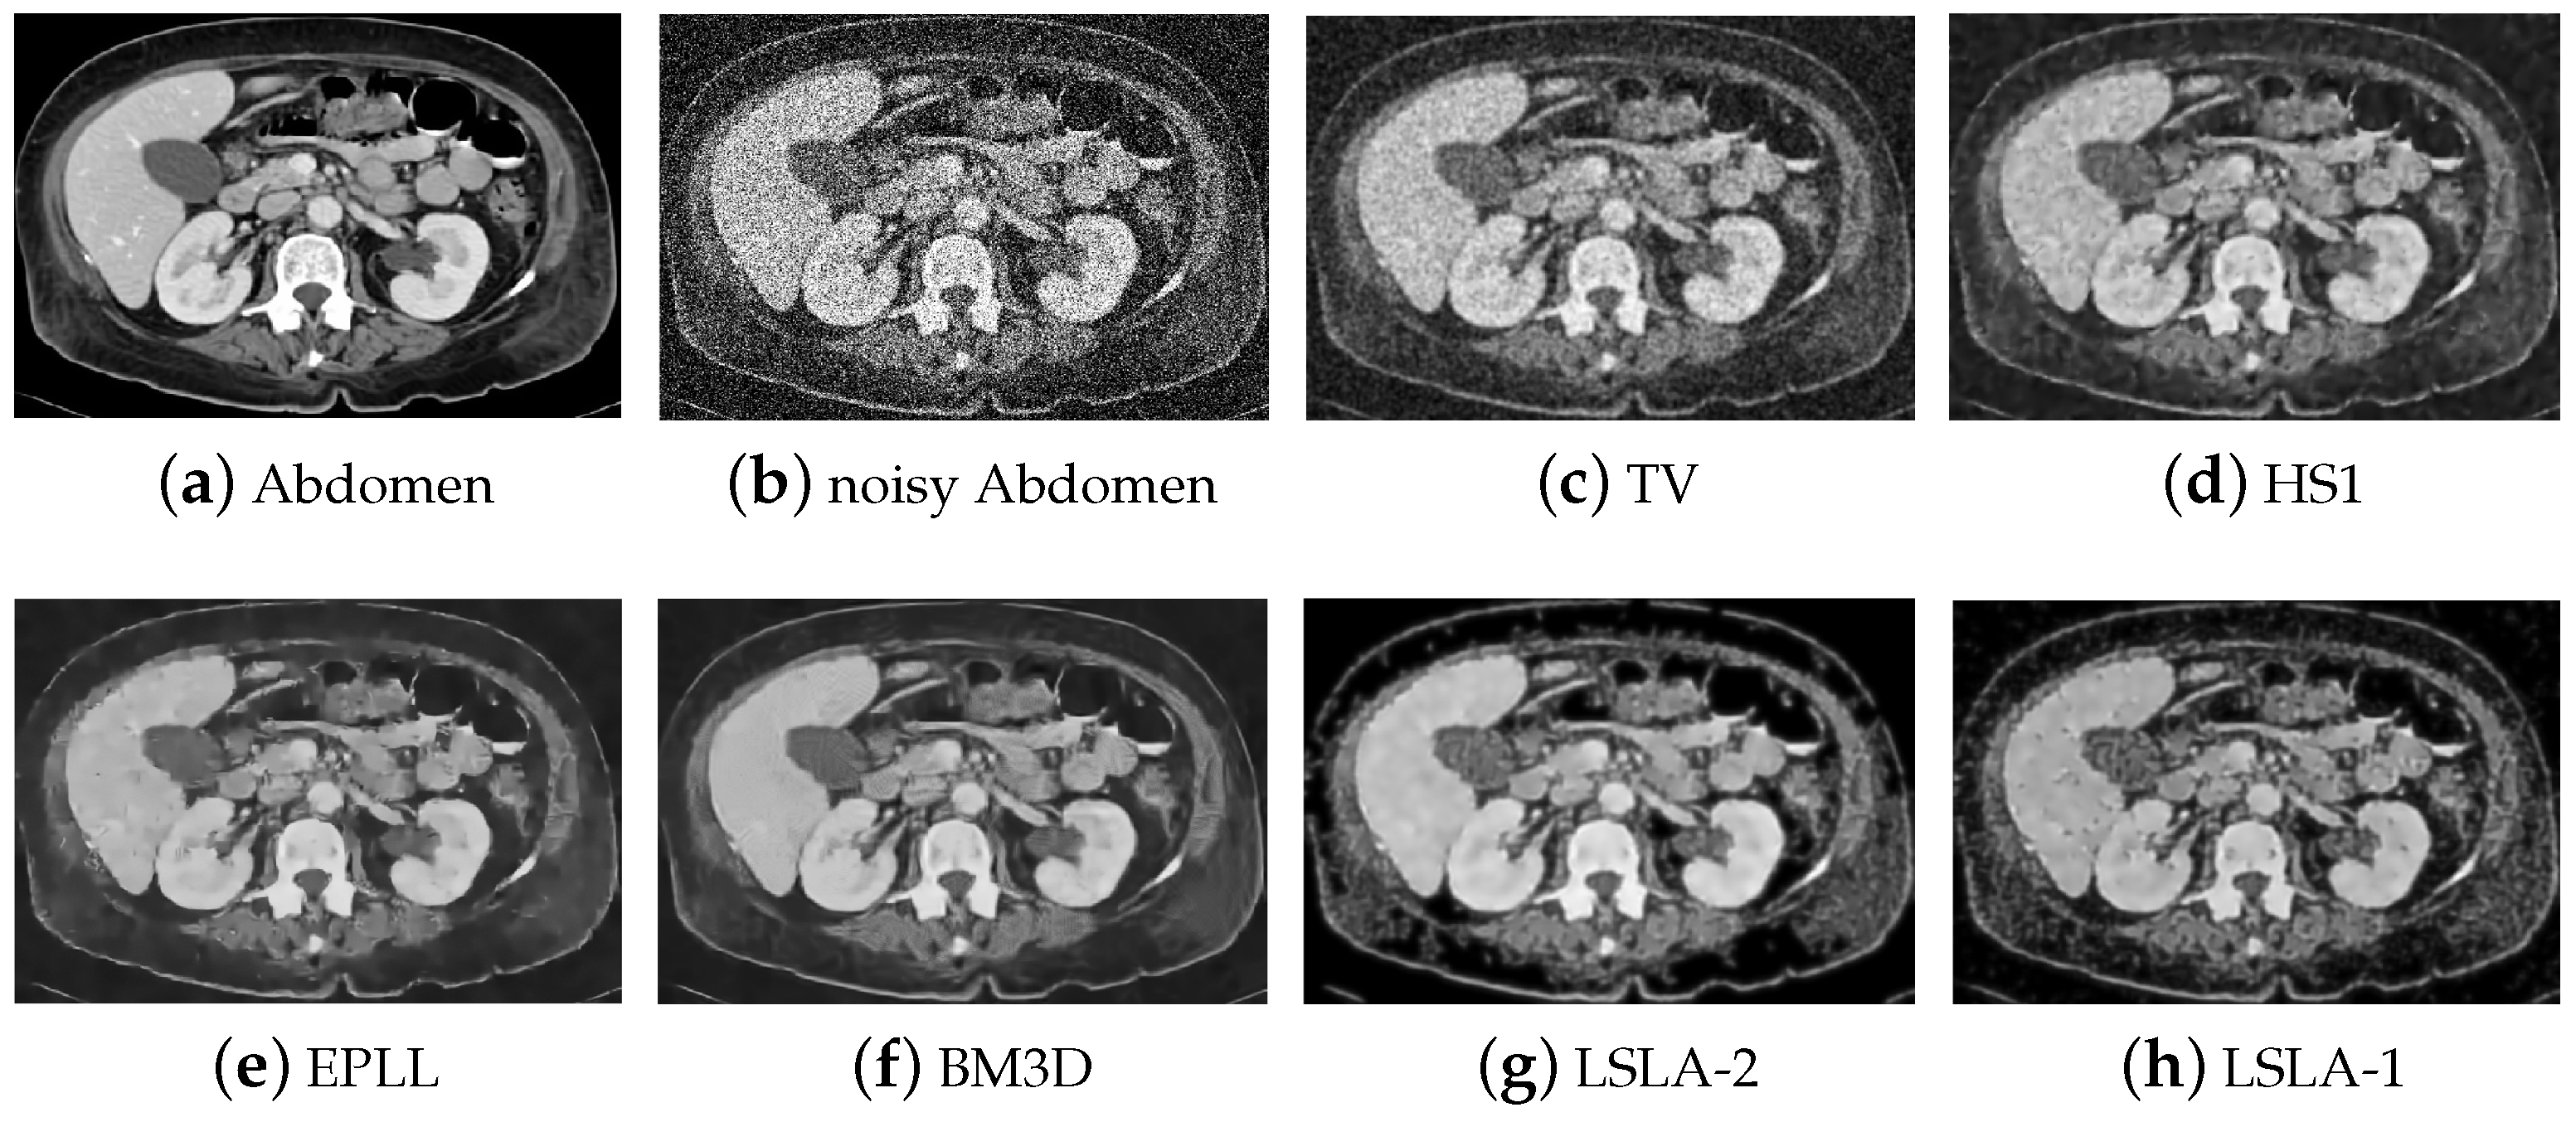

| Image | Wall | Abdomen | ||||||

| Method | TV | PSNR | 20.70 | 18.19 | 16.80 | 22.57 | 20.06 | 18.50 |

| SSIM | 0.6521 | 0.5601 | 0.4978 | 0.5579 | 0.4940 | 0.4697 | ||

| HS | PSNR | 21.33 | 18.54 | 17.03 | 23.29 | 20.52 | 18.77 | |

| SSIM | 0.7043 | 0.5975 | 0.5460 | 0.6384 | 0.5592 | 0.5300 | ||

| EPLL | PSNR | 21.36 | 18.38 | 16.76 | 23.51 | 20.64 | 18.84 | |

| SSIM | 0.7254 | 0.6254 | 0.5698 | 0.6517 | 0.5915 | 0.5440 | ||

| BM3D | PSNR | 21.97 | 19.04 | 17.42 | 24.14 | 21.26 | 19.50 | |

| SSIM | 0.7421 | 0.6410 | 0.5838 | 0.6700 | 0.6026 | 0.5603 | ||

| LSLA-2 | PSNR | 22.28 | 20.11 | 19.22 | 25.06 | 22.68 | 21.47 | |

| SSIM | 0.7598 | 0.6730 | 0.6477 | 0.7530 | 0.6680 | 0.6237 | ||

| LSLA-1 | PSNR | 22.51 | 20.31 | 19.12 | 24.97 | 22.72 | 21.37 | |

| SSIM | 0.7675 | 0.6736 | 0.6311 | 0.7462 | 0.6663 | 0.6096 | ||